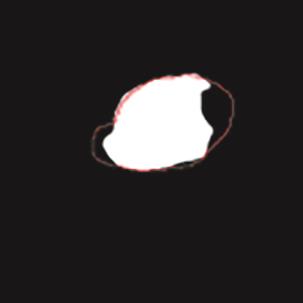

乳腺癌是全球女性最常见的恶性肿瘤之一,准确的病变分割对于乳腺癌的早期诊断与治疗具有重要意义。然而,由于病变形态的多样性以及超声成像机制的复杂性,现有基于深度学习的乳腺超声图像病变分割方法在分割准确性方面仍面临巨大挑战。为进一步提升乳腺超声图像中病变区域的分割精度,该文基于经典U-Net架构,提出了一种新型乳腺超声图像病变分割网络(CWSASKM-BBAM-Net)。首先,在网络中引入逐通道空间自适应选择核卷积模块(CWSASKM),根据不同通道的语义特征为每个空间位置自适应选择感受野大小,以增强多尺度信息的建模能力;然后,引入双向边界感知机制(BBAM),通过融合正向与反向注意力,对目标显著区域及其边界进行协同建模,同时逐步提升对非显著区域与病变区域的区分能力,以进一步强化边界信息的表达;最后,在3组公开乳腺超声图像数据集(BUSI、UDIAT和STU)上开展分割实验。结果表明:该方法在数据集BUSI上的杰卡德指数、精确率、召回率和Dice相似系数分别为71.97%、82.85%、81.40%和80.44%,较次优方法分别提升1.69、1.05、1.28和1.84个百分点;在数据集UDIAT上,这4项指标分别达到78.14%、88.31%、86.73%和86.10%,较次优方法分别提升了2.75、2.04、0.56和2.01个百分点;在外部数据集STU上,该方法也取得了优于其他方法的整体表现。实验结果表明,CWSASKM-BBAM-Net在乳腺超声图像分割任务中展现出更优的整体性能。